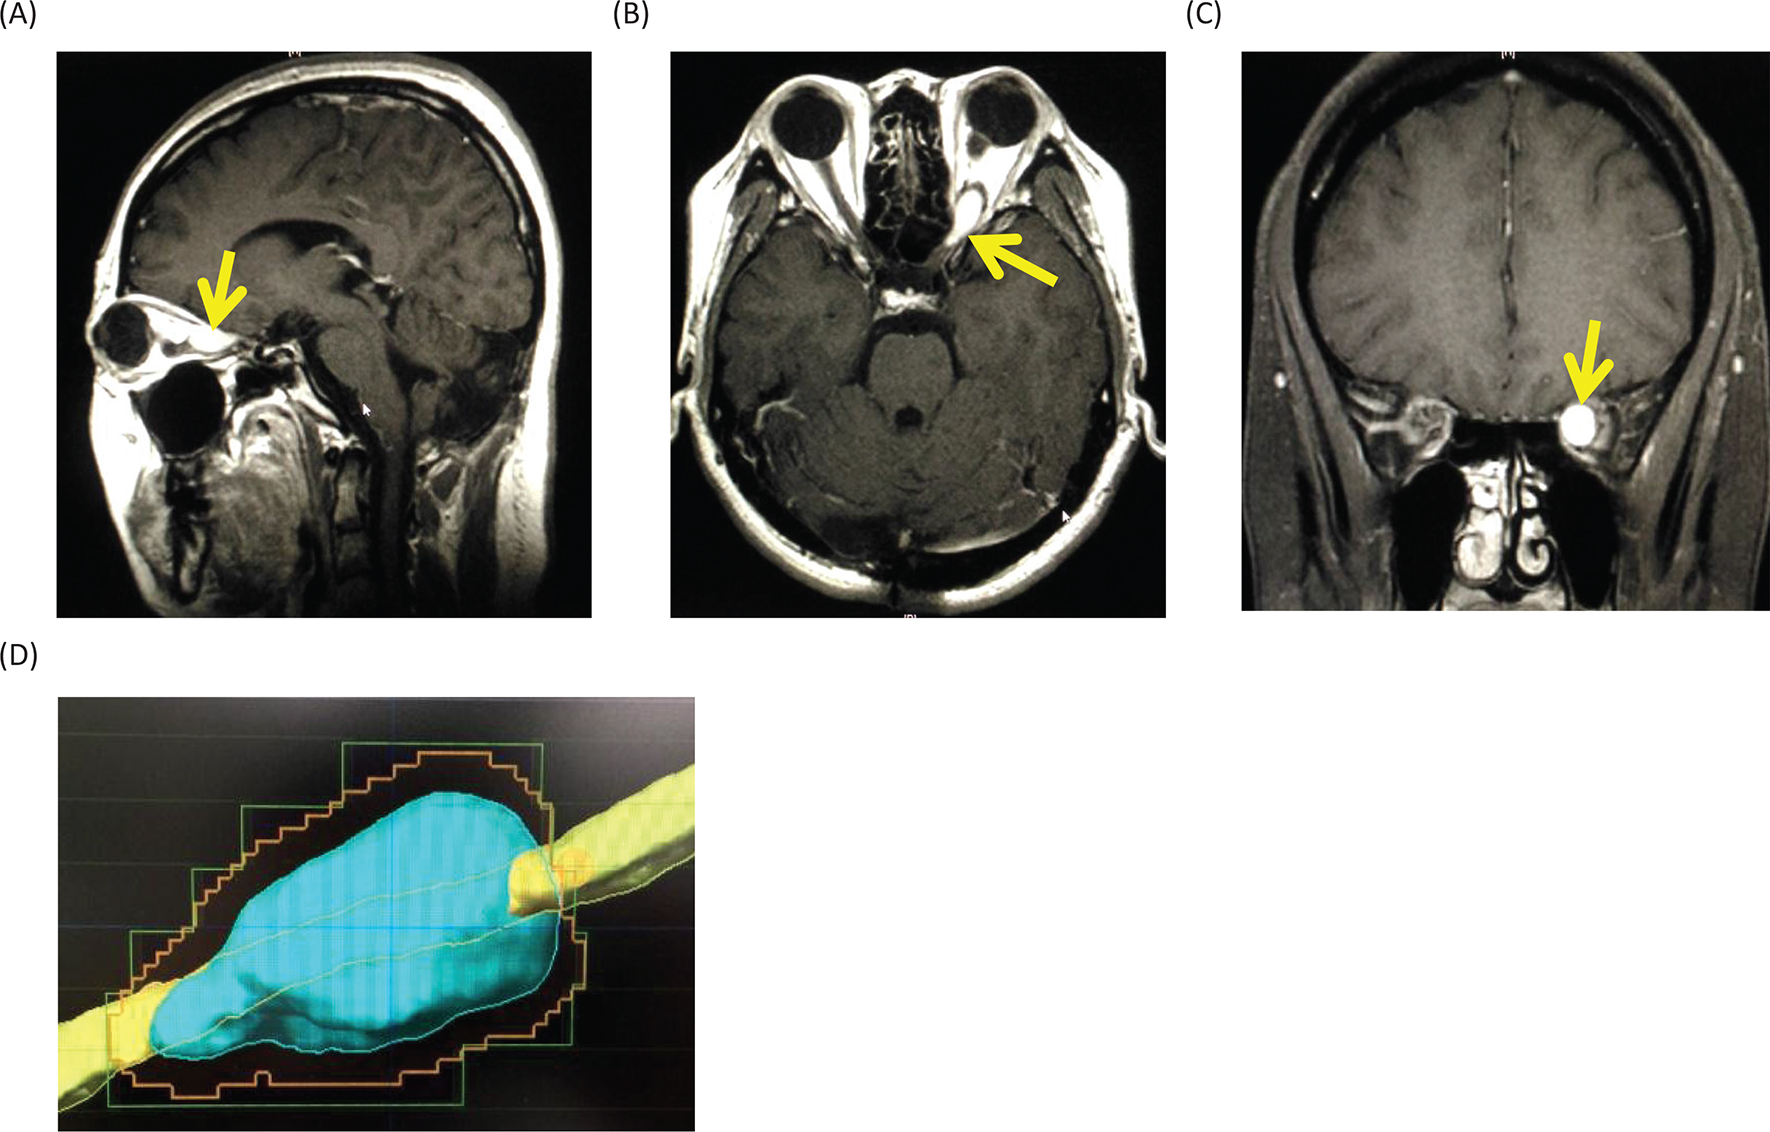

The differential diagnoses for the tumor include optic glioma, optic sheath meningioma, optic nerve schwannoma and optic nerve hemangioblastoma. Among them, since the patient is a VHL patient, the most probable diagnosis was thought to be an optic nerve hemangioblastoma. Therefore, we made a decision to treat the tumor with stereotactic radiosurgery. At Shonan Fujisawa Tokushukai Hospital, the stereotactic radiosurgery was prescribed with the dose being 39 Gy/13 fractions using Novalis. The planning target volume was set at 0.7 mL, and D95 (95% of standard irradiation volume) was set at 35 Gy/13 fractions. The patient completely lost her vision after the radiosurgery. Eighteen months after the radiosurgery, the tumor volume slightly decreased (Figure 5), but her vision has been still lost. The consent to publish the case has been given by the patient.

Fig 5

Figure 5. Gadolinium-enhanced magnetic resonance images at 18 months after the stereotactic radiosurgery. (A) Sagittal image. (B) Axial image. (C) Coronal image.